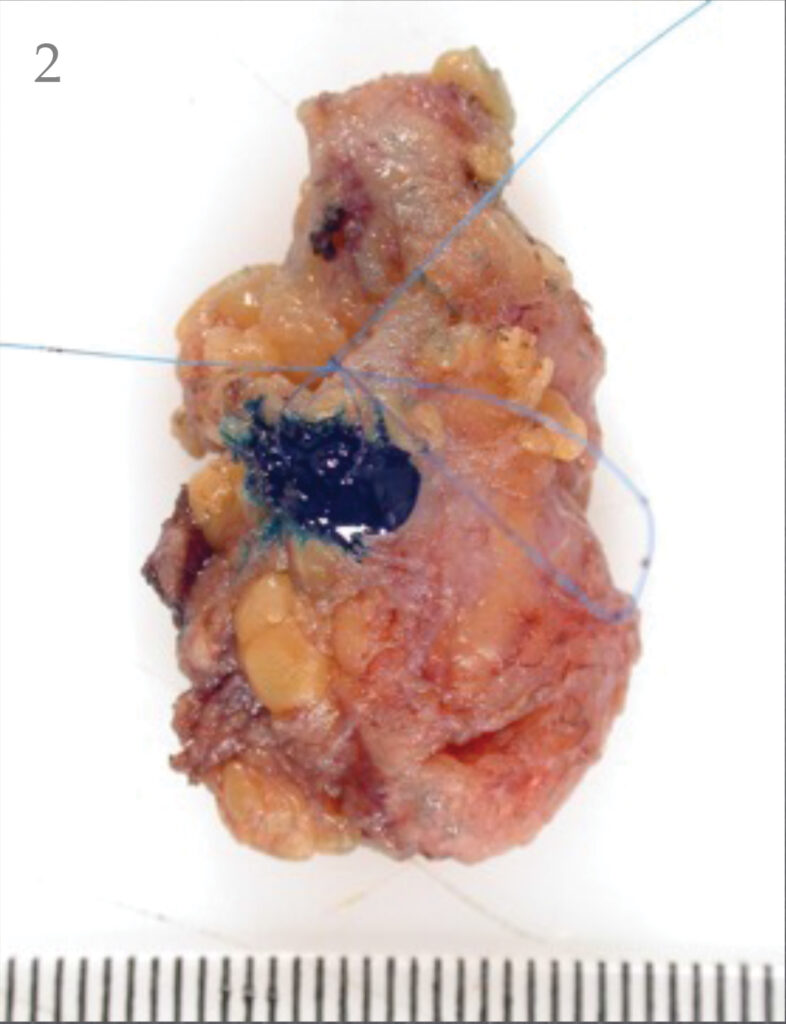

The combination of the radioactive liquid and blue dye is the best way to identify the sentinel node (shown on the next page). The nodes are arranged like a bunch of grapes.

The lymphoscintigraphy and blue dye helps your surgeon to pick out the grape within the bunch, which looks after the part of your body where your melanoma was.

There is a possibility of an allergic reaction to the dye but this is very rare. The surgeon removes that node (or in some cases 2-3 nodes), the operation is usually less than an hour. The pathologist then looks for melanoma cells in the node and the WLE under the microscope.

Pathology of sentinel node biopsy

During the following weeks the pathologist will look carefully at the removed lymph gland and the WLE, under the microscope, for tiny deposits of melanoma. These are often referred to as micro-metastases (see the picture below). Patients normally get the results 3-4 weeks after the surgery.

If a small melanoma deposit (micro metastases ) is detected then the doctor will discuss the options with you. Historically this may have involved removing the remaining nodes. This is known as a lymph gland dissection/completion lymphadenectomy/ lymph node clearance. If micro-metastases are detected (a positive sentinel node biopsy) then the doctor will discuss management of this with you.

If the deposits of melanoma found are larger or there are multiple deposits, they may recommend that the rest of the glands in this area be removed. This is known as a lymph gland dissection/completion lymphadenectomy/lymph node clearance.

- Sentinel node with radioactive hotspot marked.

- Sentinel node with hotspot inked.

- Sentinel node with hotspot ink visible.

- Sentinel node pathology with hotspot ink visible near the melanoma deposit in the node.